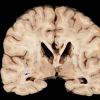

INFECTION

PML (JC Virus)

PML - Gross Pathology (2)